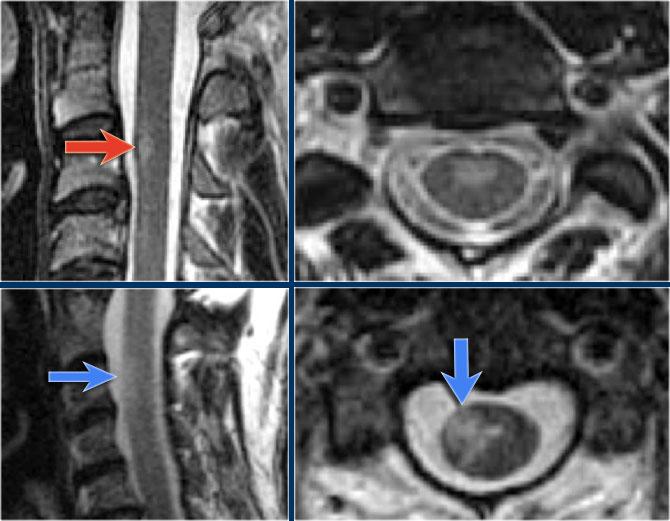

Bên trái là hình ảnh của bệnh nhân nam 60 tuổi mắc u tế bào hình sao.

Bệnh nhân nhập viện với đau vùng ngực và rối loạn cảm giác chi dưới trái, tiếp theo là liệt nửa người trái.

Có tăng tín hiệu đa đoạn trên chuỗi xung T2W kèm phù nề nhẹ, tương tự như hình ảnh đã thấy trong các trường hợp TM.

Trên CE-T1W có vùng ngấm thuốc tương phản từ.

Vùng ngấm thuốc có hình thái nghiêng về u hơn, nhưng việc phân biệt vẫn còn khó khăn.

Như vừa đề cập, chẩn đoán phân biệt chính của các bệnh lý tủy sống đã thảo luận là u tế bào hình sao.

U tế bào hình sao là loại u thâm nhiễm lan tỏa, không có hình thái khối rõ ràng.

Thường có hình ảnh ngấm thuốc không đồng nhất theo từng vùng.

Hình bên trái là u tế bào hình sao ở bệnh nhân 66 tuổi, nhập viện vì các triệu chứng cảm giác tiến triển dần.

Sinh thiết xác nhận chẩn đoán u tế bào hình sao.

Tiếp tục theo dõi hình ảnh tái khám.

Bệnh nhân không có chỉ định phẫu thuật và hình ảnh tái khám cho thấy bệnh tiến triển.